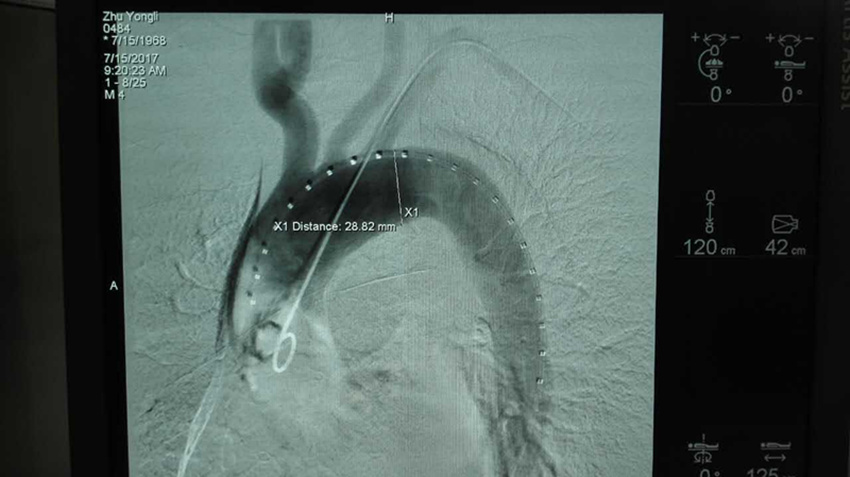

7月15日上午9时,由普外二科汪志刚医师、张文俊主任手术,陆信武教授现场指导,为患者施行局麻,在DSA引导下行经右股动脉穿刺主动脉造影术+主动脉夹层腔内修复术,9:50手术顺利完成。目前病人一切正常,生命体征平稳。

成功植入大血管支架